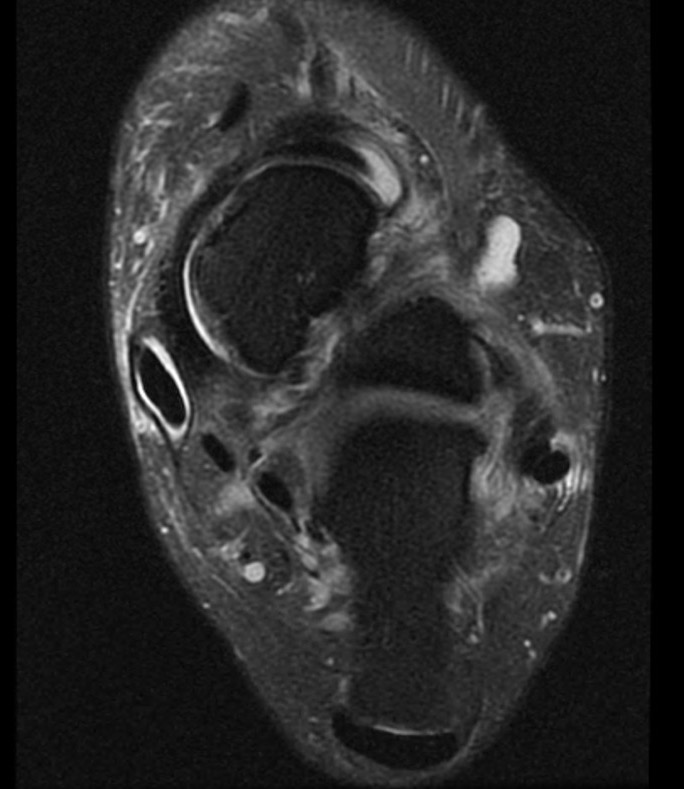

MRI

Tendonitis - fluid around tendon

Tendinopathy - tendon thickening

Tears

Tibialis posterior tendonitis

Tibialis posterior tendinopathy